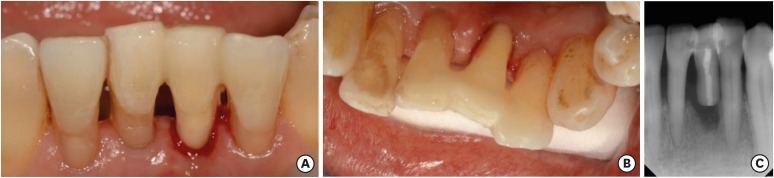

A 66-year-old man visited our department because of severe mobility of the left mandibular central incisor (tooth #31). The tooth showed degree 3 mobility and slight tenderness on percussion. Clinical and radiographic examinations revealed that the tooth was root-fractured at the apical third. The tooth was diagnosed with apical root fracture and chronic periodontitis (Figure 9). The tooth needed extraction, but patient was concerned about the high costs of an implant or fixed partial denture. Therefore, a direct FRC bridge was chosen as a treatment and patient consent was obtained.

Figure 9

Preoperative view. (A) Intraoral photograph (labial view); (B) intraoral photograph (lingual view); (C) periapical view.